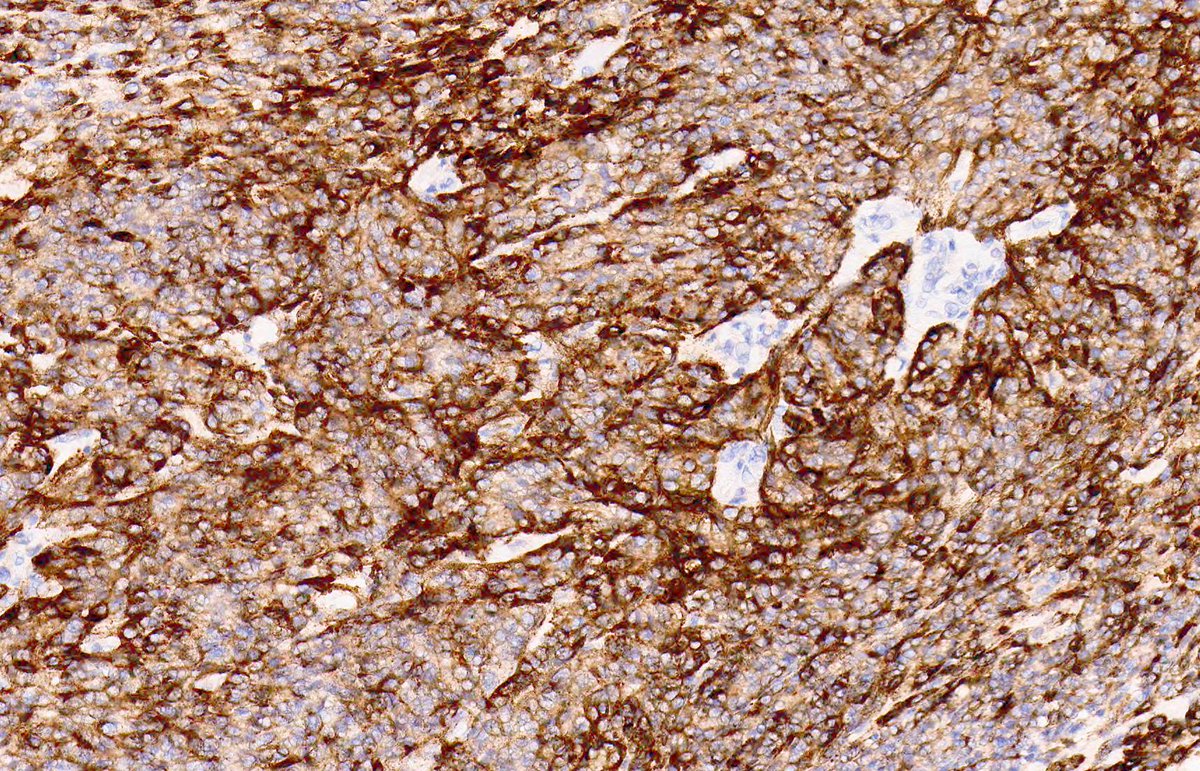

KAPOSI SARCOMA: IHC: HHV8. NB: ectatic, irregularly shaped, thin-walled vessels; collagen dissection; so-called 'promontory sign'; attenuated endothelial cells with eosinophilic cytoplasm; hyperchromatic nuclei showing mild atypia and inconspicuous mitotic activity.

2

28

69